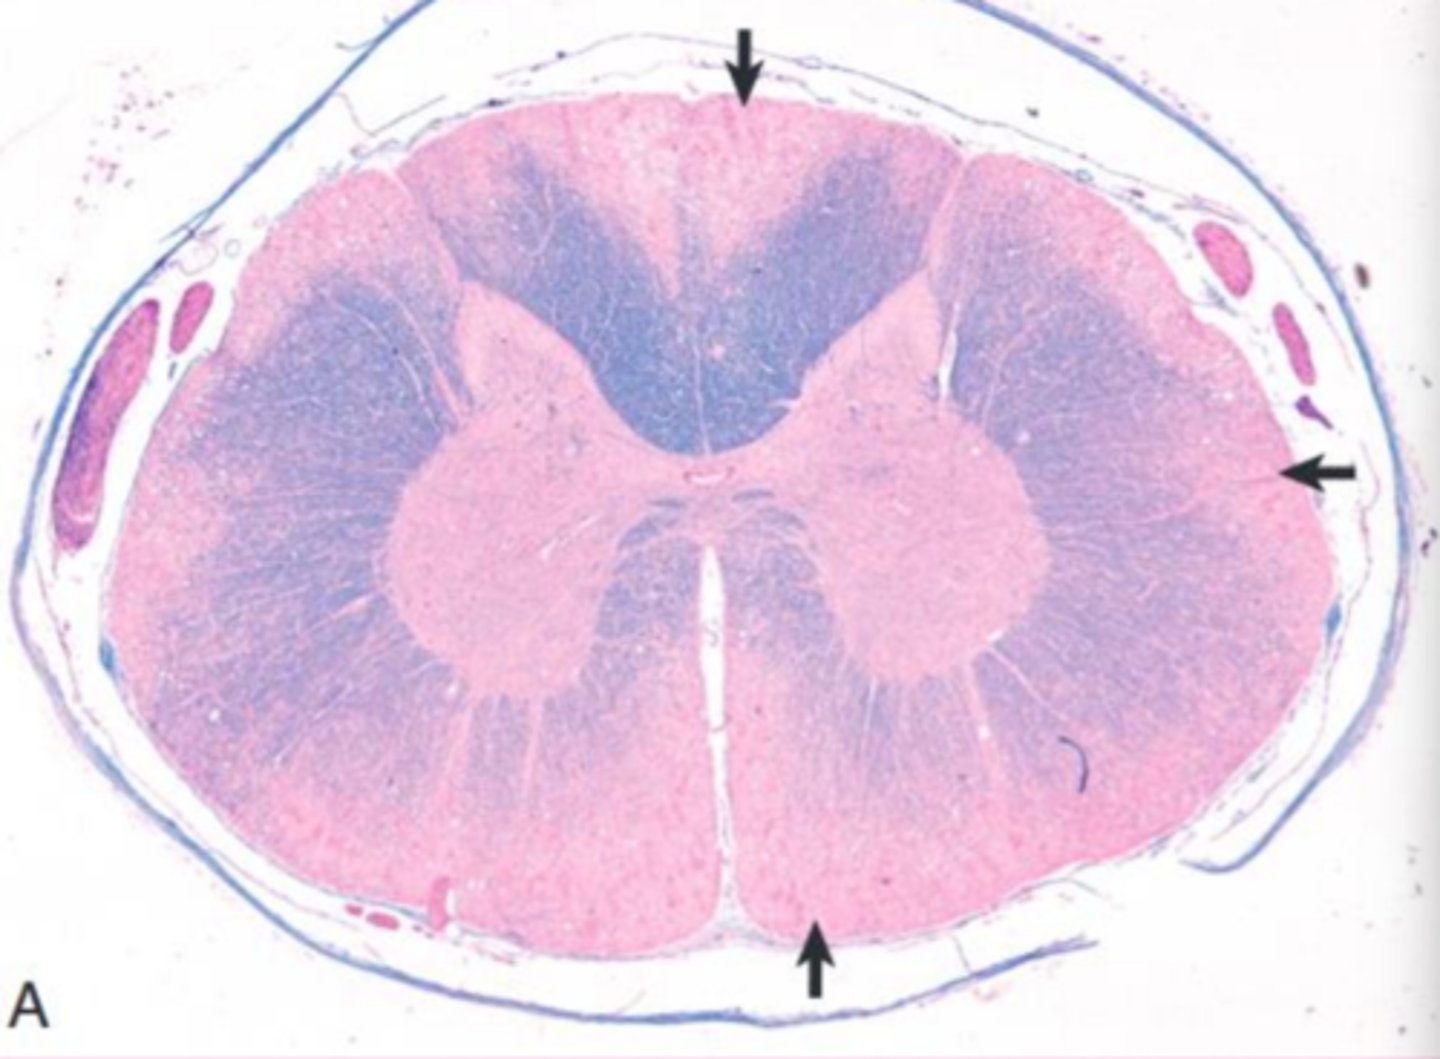

globoid cell leukodystrophy

What?

<p>What?</p>